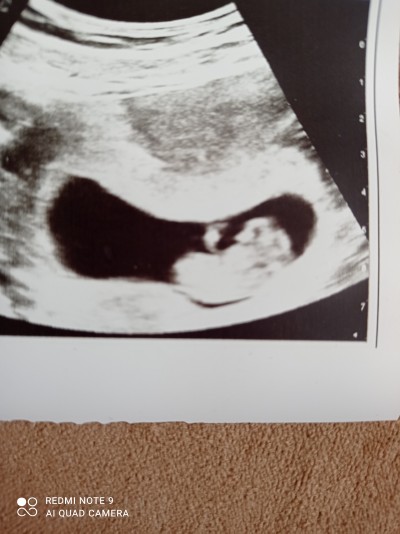

Kizlar 11 haftalik gebeyim bugun devlet hastanesine gittim tahmin istedim ve erkege benzer bu haftada dedi bnde erkek mi dedim kizda olsa erkege benzer dedi geri anlamadim devlet ya soylemek mi istemedi acaba .bi tanidikta ultrason fotosuna bakti bu kiz dedi kese seklimden dolayi anlamadim fikrinolan varmi

Kese şeklime göre erkek gibi duruyor. Haftan erken oldugu için. Cinsiyet olusurken ilk basta ikiside kıza bence. Erkeğinki sonradan değişir.

Canım kese yuvarlak veya oval olursa bebek kız muz şeklinde ***** olursa erkek. İki kızım var iki kızınki öyle yuvarlaktı.şimdiki erkek dedikleri gibi muz şeklinde. Birde fark ettiğim şu erkekte idrar acık sarı kızda kırmızıya benziyor

Keseden erkeğe benziyo benimkide böyleydi kese

Kuzum benim köşemde böyleydi kızım olcak oğlumda üçgen gibiydi ama tesadüf olduğunu düşünüyorum 11 haftada çok erken en az 13 haftalık olman lazım ki devlette 16 haftadan önce söylemiyorlar

yuvarlak olunca kiz fasulye gibi olunca erkek diyorlar. benim fasulye gibiydi ama kizim olcak.Kese olayi dogru degil bence

Keseden belli olmaz ki ya milletin uydurması benimkine de kese şekline filan erkek dediler kız çıktı